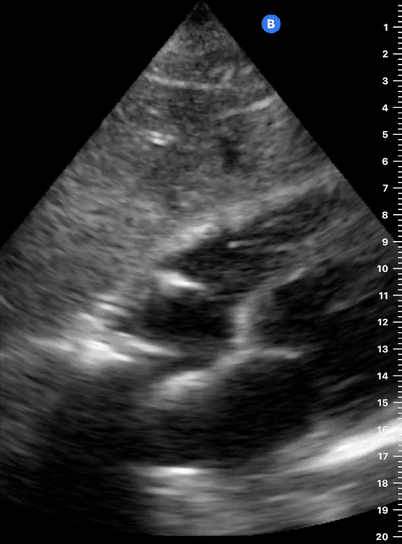

As the transverse (short-axis) images show the relative wall thickness and contractility, this view is the best for assessing regional wall motion. Also, the inferior portion of the view (papillary muscles) is ideal for comparing the relative size of both ventricles. In expert hands, the superior portion of the view allows evaluation of the aortic valve and RV overload.

While maintaining the short axis, sweep or gently fan the probe along the long axis to obtain a series of ‘sectional’ views of the LV and RV.